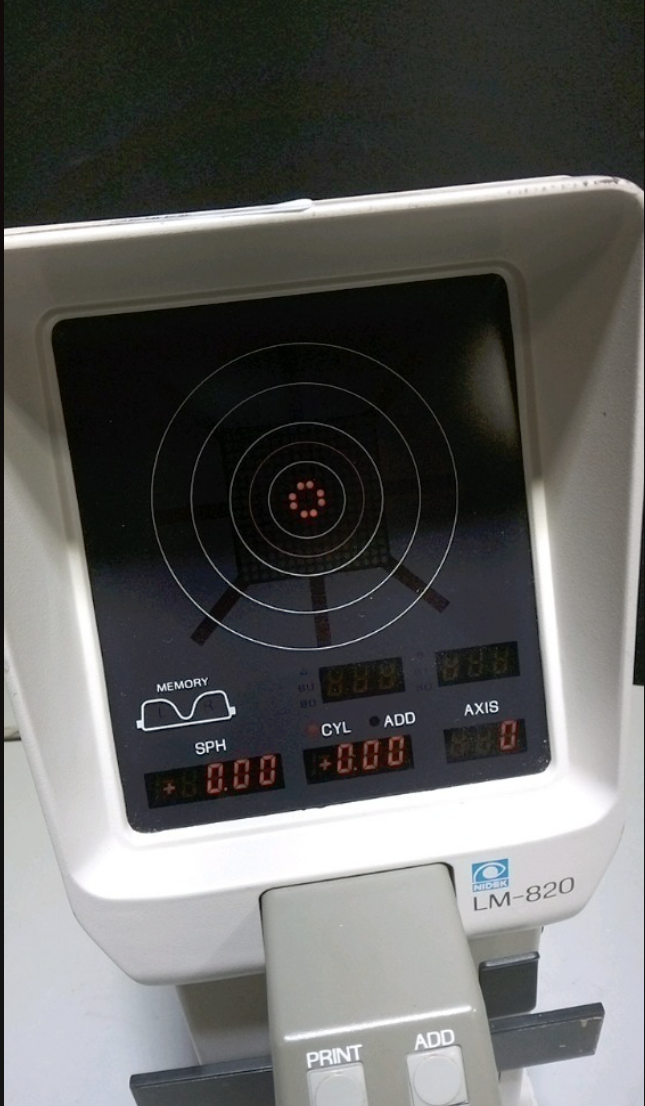

DIAGNOSTIC ULTRASOUND MACHINES FOR SALE

GE 3C-RS ULTRASOUND PROBE TRANSDUCER 2013

Sale price$ 2,368.40